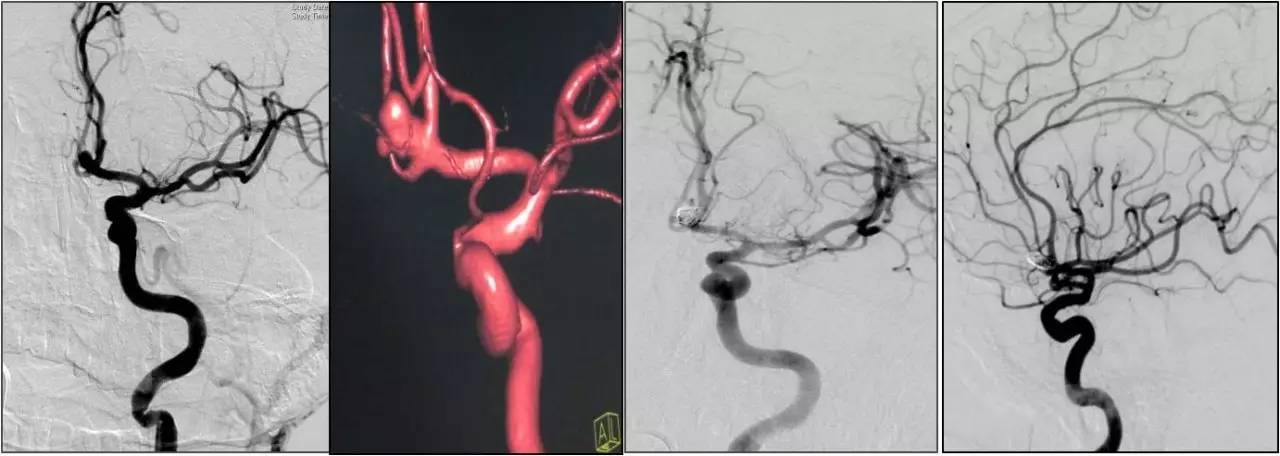

(三)颅内外动脉血管成形术

模式图

病例1:颈内动脉起始段狭窄

》男性,65岁,因发作性右侧肢体活动不灵7天入院。发作时不能行走及持物,言语表达困难,持续约10分钟左右,自行完全恢复正常,7天来共发作3次,每次发作症状基本相同。

》入院时查体:神经系统查体未见阳性定位体征。

病例2:大脑中动脉M1段狭窄

》男性,56岁,因反复右肢体无力,每次发作约数分钟自行缓解。经药物治疗3个月TIA仍反复发作既往有高血压病史10年,糖尿病病史8年。

》自带CT提示:多发腔隙性脑梗死。入院诊断:TIA,高血压病,糖尿病。行全脑血管造影,发现左大脑中动脉M1段狭窄,狭窄处植入了支架。

病例3:椎动脉开口狭窄

》女性,65岁,间断头晕6个月、加重2天为主诉入院。 Ø头颅CT未见明显异常。头颅MRI示脑干、右侧小脑可见斑点状长T1长T2信号影,Flair呈高信号,DWI呈低信号。

》DSA检查可见左侧椎动脉起始段中度狭窄,行支架置入术后,患者头晕症状明显缓解。